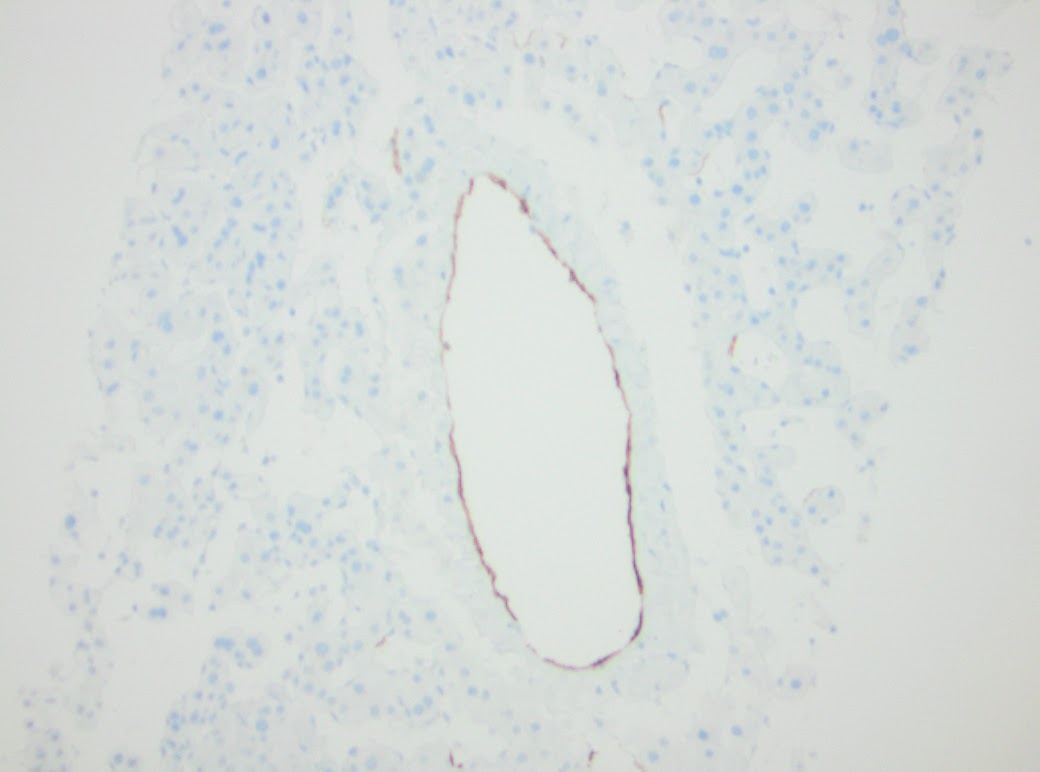

February and June 2015 needle core biopsies were performed. Provided for review are two parts of core needle biopsies obtained from 2015. The first core needle biopsy from February of 2015, site unspecified consists of three portal tracts without significant fibrous expansion. No steatosis or significant histopathologic findings are seen. The second specimen labeled mid lesion #2 shows quite different histopathologic findings of striking sinusoidal dilation and corresponding hepatocyte atrophy (see Figure 1).

There is one vascular structure with fibrin within the lumen. No significant macrovesicular steatosis or inflammation is seen in either of the two liver biopsies. There are focal areas of hemorrhage and other areas with hepatocyte dropout. Another liver biopsy was obtained from the patient four months later in June of 2015. Again, striking zone 3 hepatocellular atrophy and sinusoidal dilatation was seen (Figure 2.) Fibrin was identified in several of the portal venules (Figure 3).

| Figure 1. February 2015 biopsy 20X. |